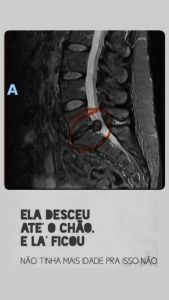

A participação de Ana Paula Renault no BBB 26 colocou sua saúde em evidência. Durante o confinamento, a jornalista mineira, que integra o grupo dos veteranos, relatou diversas vezes dores na coluna e chegou a deixar de cumprir atividades em razão de um diagnóstico recente de hérnia de disco.

Em maio do ano passado, Ana Paula passou por uma cirurgia (discectomia endoscópica) na coluna após exames constatarem uma "hérnia gigantesca" que, segundo ela, já estava tendo comprometimento neurológico. Na época, ela afirmou que não conseguia sentir os dedos do pé esquerdo.